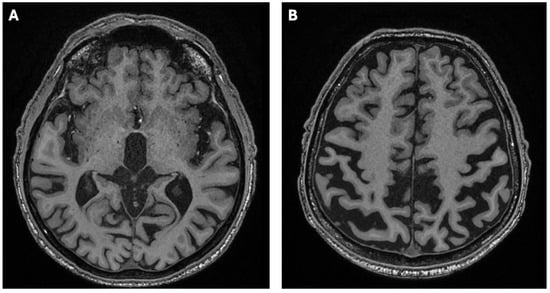

2. Case Report